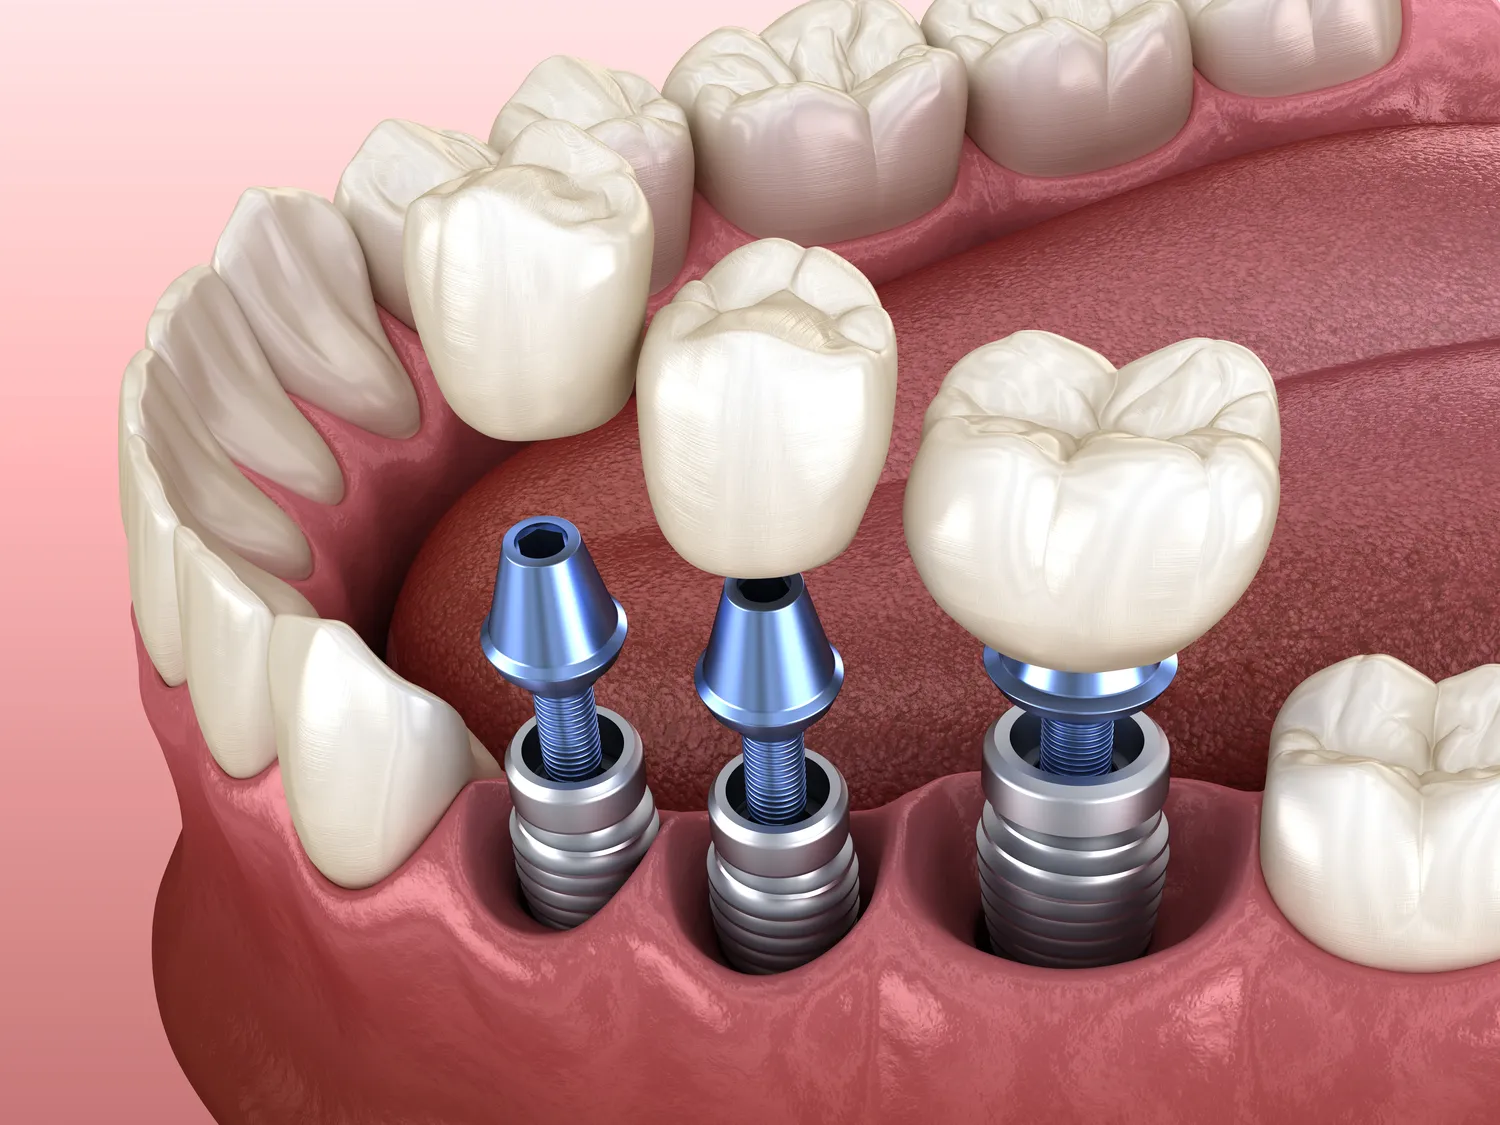

Implanty w jeden dzień w Koszalinie to rozwiązanie, które zyskuje coraz większą popularność wśród pacjentów poszukujących szybkiej i efektywnej metody odbudowy uzębienia. Jedną z głównych zalet tego typu zabiegu jest znaczna oszczędność czasu. Pacjenci nie muszą czekać na gojenie się dziąseł oraz na osadzenie implantu, ponieważ wszystko odbywa się podczas jednej wizyty. To idealne rozwiązanie dla osób, które prowadzą intensywny tryb życia i nie mogą sobie pozwolić na długotrwałe leczenie stomatologiczne. Kolejnym atutem jest minimalna inwazyjność zabiegu, co oznacza mniejsze ryzyko powikłań oraz szybszy proces rekonwalescencji. Dzięki nowoczesnym technologiom oraz materiałom wykorzystywanym do produkcji implantów, pacjenci mogą cieszyć się trwałym i estetycznym efektem końcowym. Warto również wspomnieć o tym, że implanty w jeden dzień są często bardziej opłacalne finansowo, ponieważ eliminują konieczność wielokrotnych wizyt u stomatologa oraz związanych z nimi kosztów.

Proces zakupu implantów w jeden dzień w Koszalinie zaczyna się od konsultacji ze specjalistą, który oceni stan zdrowia jamy ustnej pacjenta oraz zdecyduje o możliwości przeprowadzenia zabiegu. Na tym etapie lekarz wykonuje dokładne badania diagnostyczne, takie jak zdjęcia rentgenowskie czy tomografia komputerowa, aby dokładnie zaplanować cały proces. Po potwierdzeniu kwalifikacji do zabiegu następuje przygotowanie do operacji. W dniu zabiegu pacjent otrzymuje znieczulenie miejscowe lub ogólne, w zależności od indywidualnych potrzeb oraz preferencji. Następnie lekarz przystępuje do wszczepienia implantu, co zazwyczaj zajmuje kilka godzin. Po zakończeniu procedury pacjent otrzymuje instrukcje dotyczące pielęgnacji oraz diety na najbliższe dni. Ważne jest również umówienie się na wizyty kontrolne, aby monitorować proces gojenia oraz upewnić się, że implanty przyjmują się prawidłowo.

Proces integracji implantu po wszczepieniu w Koszalinie to kluczowy etap leczenia stomatologicznego, który decyduje o trwałości i funkcjonalności implantu. Zwykle trwa on od kilku tygodni do kilku miesięcy, a jego długość zależy od wielu czynników, takich jak stan zdrowia pacjenta, jakość kości szczękowej czy technika przeprowadzonego zabiegu. W przypadku zdrowych pacjentów z odpowiednią ilością kości proces integracji może przebiegać szybciej; natomiast osoby z problemami zdrowotnymi lub niewystarczającą ilością kości mogą potrzebować dodatkowych procedur przed wszczepieniem implantu lub dłuższego czasu gojenia. Podczas tego okresu ważne jest regularne monitorowanie stanu zdrowia przez stomatologa; wizyty kontrolne pozwalają ocenić postęp gojenia oraz wykryć ewentualne komplikacje we wczesnym stadium.